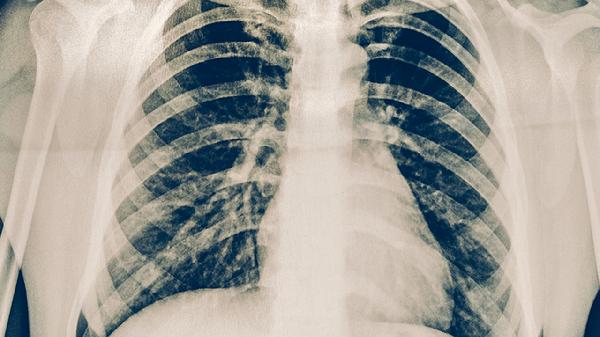

肺结核的典型症状包括咳嗽咳痰、咯血、胸痛、发热盗汗、消瘦乏力等。肺结核是由结核分枝杆菌感染引起的慢性传染病,主要累及肺部但也可侵犯其他器官。

持续两周以上的慢性咳嗽是肺结核最常见症状,初期多为干咳,随着病情进展可出现黄白色黏痰。当合并支气管结核时可能出现刺激性呛咳,这种咳嗽往往在晨起时加重,夜间平卧也可能诱发咳嗽。部分患者痰中可带有血丝,这与肺部病灶侵蚀小血管有关。

约三分之一的肺结核患者会出现咯血症状,轻者表现为痰中带血,重者可出现大咯血。咯血通常是由于肺部病灶侵犯血管所致,在空洞型肺结核患者中更为常见。大咯血时血液可呈鲜红色,伴有血块,需要紧急医疗干预以防窒息。

肺结核引起的胸痛多表现为病变部位隐痛或钝痛,咳嗽或深呼吸时疼痛可能加重。胸痛的发生与胸膜受累有关,当炎症波及壁层胸膜时疼痛会更为明显。部分患者可能伴有胸腔积液,导致呼吸困难等症状。

午后低热是肺结核的特征性表现,体温多在37.5-38.5℃之间,伴有面部潮红。夜间盗汗表现为入睡后大量出汗,可浸湿衣物。这些症状与结核杆菌释放的毒素及机体免疫反应有关,在疾病活动期尤为明显。

肺结核患者常出现进行性体重下降和疲乏无力,这与慢性消耗、食欲减退及结核中毒症状有关。严重者可出现恶病质状态,表现为明显消瘦、肌肉萎缩。儿童患者可能出现生长发育迟缓,长期患病会影响营养吸收。

肺结核患者应注意保持室内空气流通,避免密切接触他人以防传播。饮食上要保证足够热量和优质蛋白摄入,如鸡蛋、牛奶、瘦肉等,同时补充新鲜蔬菜水果。适当进行散步等温和运动有助于改善肺功能,但要避免剧烈活动。出现症状应及时到结核病定点医疗机构就诊,严格遵医嘱完成6-8个月的规范抗结核治疗,不可自行停药。治疗期间要定期复查胸部影像学和痰结核菌检查,密切观察药物不良反应。